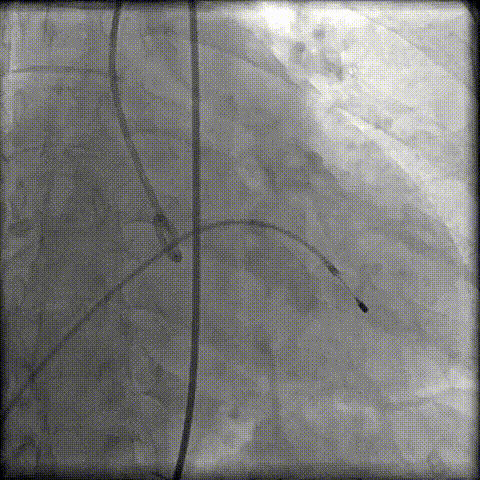

术前冠脉评估

“右足”+“左头”根部造影评估

第一次定位释放

工作位瓣膜“上跳“,完全回收后二次定位